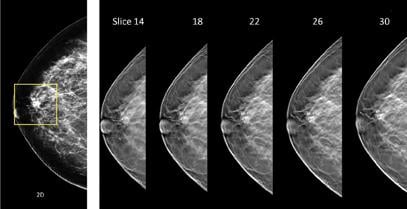

Insurance coverage mandates pertaining to “other exams deemed necessary by a physician” in some states should also be considered, given the many imaging technologies that have potential for use in breast cancer screening. Tomosynthesis has perhaps attracted more attention than any other breast imaging technology in recent years due to its ability to improve cancer detection accuracy and reduce patient recalls when combined with mammography. This technology acquires images at several angles while sweeping along a short arc over the breast, providing several image slices that allow users to visually “scroll through” breast tissue during the review of exams.

Integrating tomosynthesis into a mammography screening protocol involves minimal changes, given that tomosynthesis scans can be acquired in less than 20 seconds during the same breast compression used for mammography. However, there are currently a number of drawbacks to this technology, including the extra time that is needed to interpret the multitude of images that are acquired, increased image data storage requirements, additional ionizing radiation per exam and a lack of additional reimbursement.